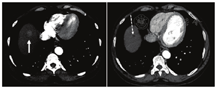

首次术后随访应该在治疗后1~3个月进行,采用腹部增强CT或MR,虽然术后3~6个月才是最佳观察时期[9]。尽管肿瘤在2种影像上表现不同,但治疗反应的特征相似[46]。如果治疗成功,则随着肿瘤血管的减少,肿瘤的大小和增强将减弱,范围与肿瘤坏死相一致(图6)。MRI的弥散受限将增加,因坏死组织的细胞膜完整性受损。经过90Y微球选择性内放射治疗后,一部分肿瘤大小可能反常增加;但是,任何大小的增加通常都是继发于周围正常肝实质细胞的死亡,不应错误地解释为肿瘤生长。治疗后影像复查中的另一个需要注意的陷阱是坏死腔周围的环形强化,有时它会被误解为肿瘤残留,但实际上它代表了肿瘤治疗后的纤维化。如果进行随访PET显像,则提示病灶缩小和代谢下降。术后成像还可以评判是否发生90Y微球选择性内放射治疗后并发症。